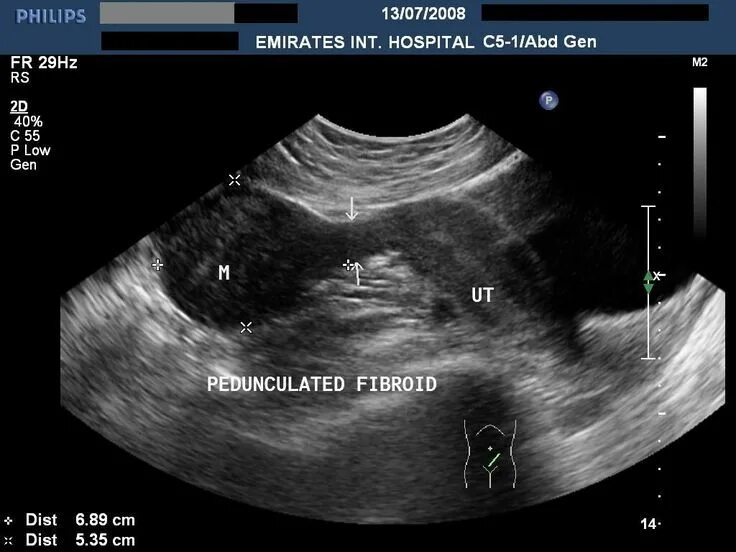

Можно ли беременность перепутать с миомой